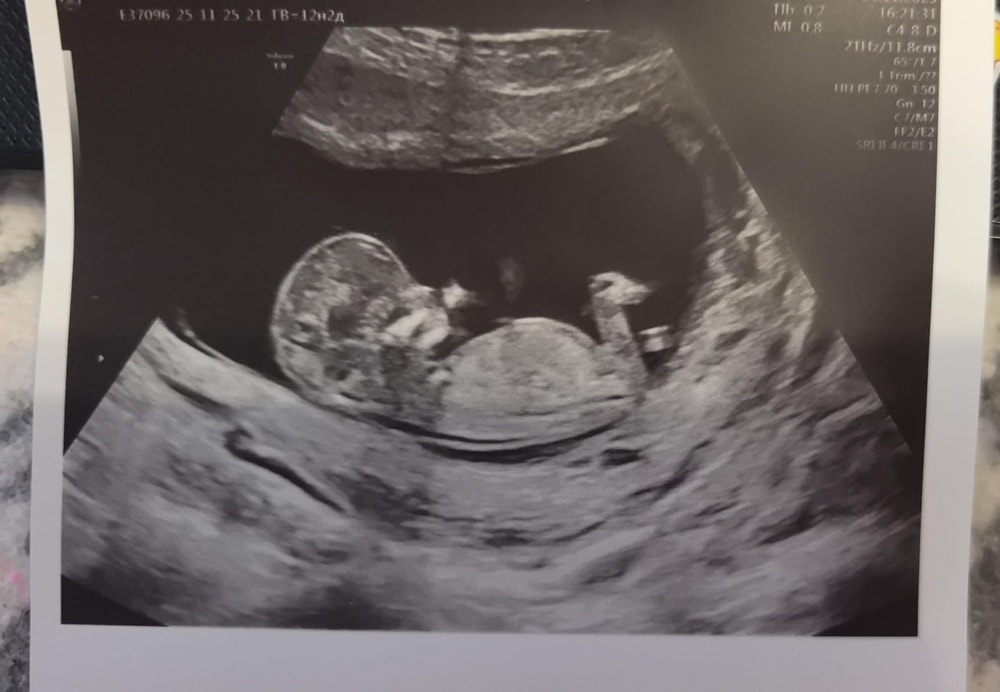

Узи и первый скрининг. Пол??

Анализы, скринингиВот и прошел наш первый скрининг. С человечком все хорошо, махал ручкой. Все соответствует нормам. Получилась такая картиночка. Кто разбирается, предположите пол, очень интересно.) +в комментарии

Мальчик , но фото не очень, поскольку половой бугорок не понятен.По черепу мальчик.

Тут не видно полового бугорка к сожалению , может есть другие снимки …. А так гадать только ) мне интуитивно девочка кажется 👐🏻🌷